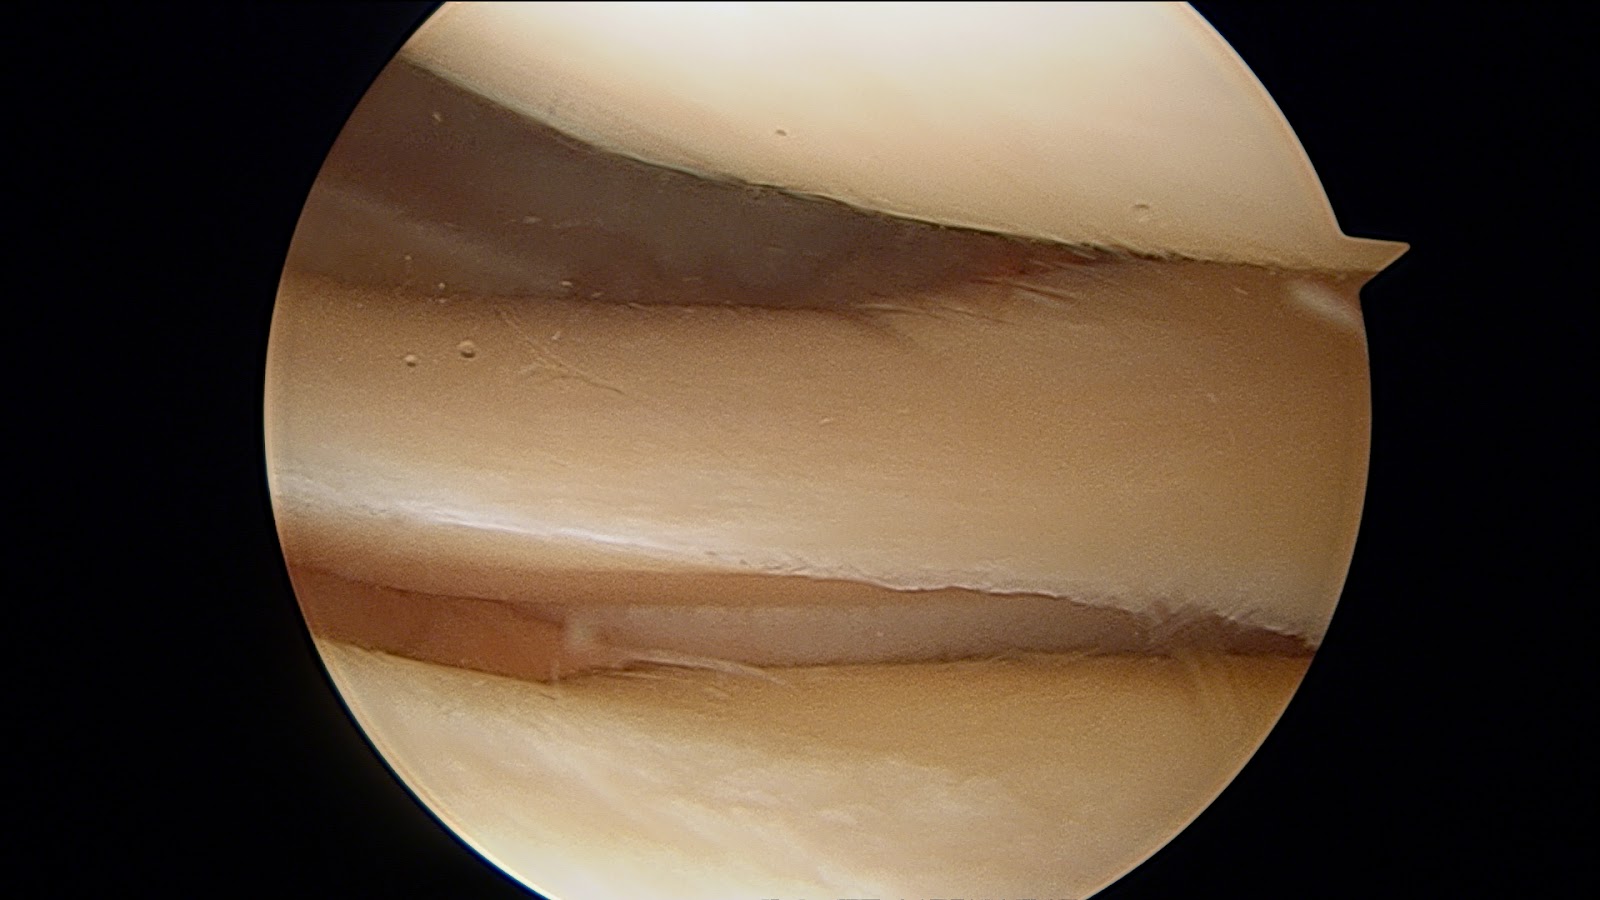

Imagen: se aprecia un menisco degenerativo (envejecido, deflecado) visto con artroscopia.